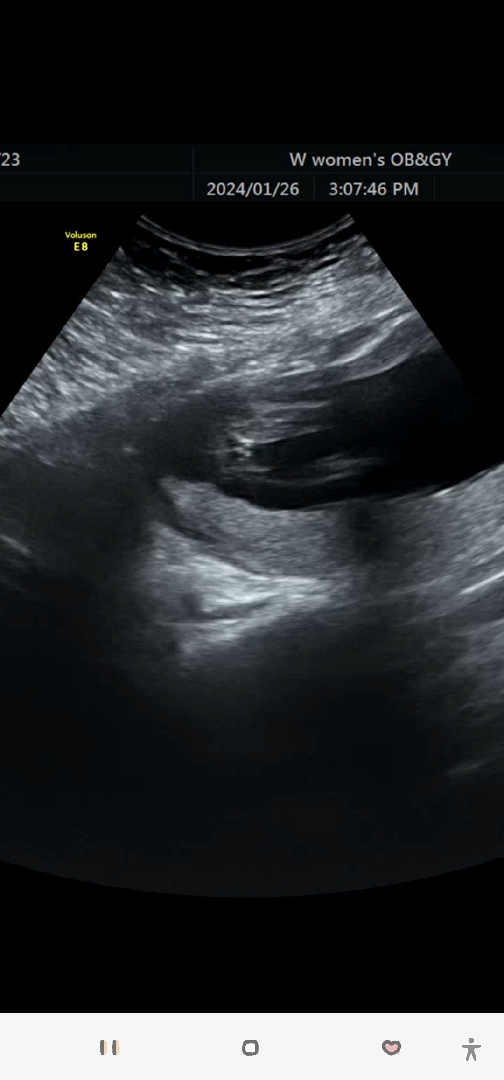

선생님이 아리까리한다는데🤣 저는 아무리봐도 딸같은데 다들 생각 어떠세요???? 다른 허벅다리쪽 찍은것도 쫌 아리까리해요🤣

딸같아보여요 아들이라기엔 뭐가너무안보이는데요? 숨겨져있는게아니라면 딸이지않을까싶네요

쪼끔 조심스럽지만 묘하게 가운데 손가락 욕할때 그 모양이 보이는게 저는 아들처럼 보입니당🙂